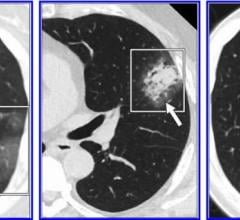

Computed tomography (CT) systems use a series of X-ray images to create an image volume dataset with slices that can be manipulated on any plane using advanced visualization software. The section includes computed tomography scanners, CT contrast agents, CT angiography (CTA and CCTA), CT perfusion, spectral CT (dual-source CT), and iterative reconstruction dose reduction software.

May 21, 2020 — RADLogics announced that its AI-powered medical imaging applications designed to assist in the detection ...

April 21, 2020 — RADLogics announced new worldwide deployments and installations of the company’s AI-powered solution to ...

April 17, 2020 — To date, the radiology literature on coronavirus disease (COVID-19) pneumonia has consisted of limited ...